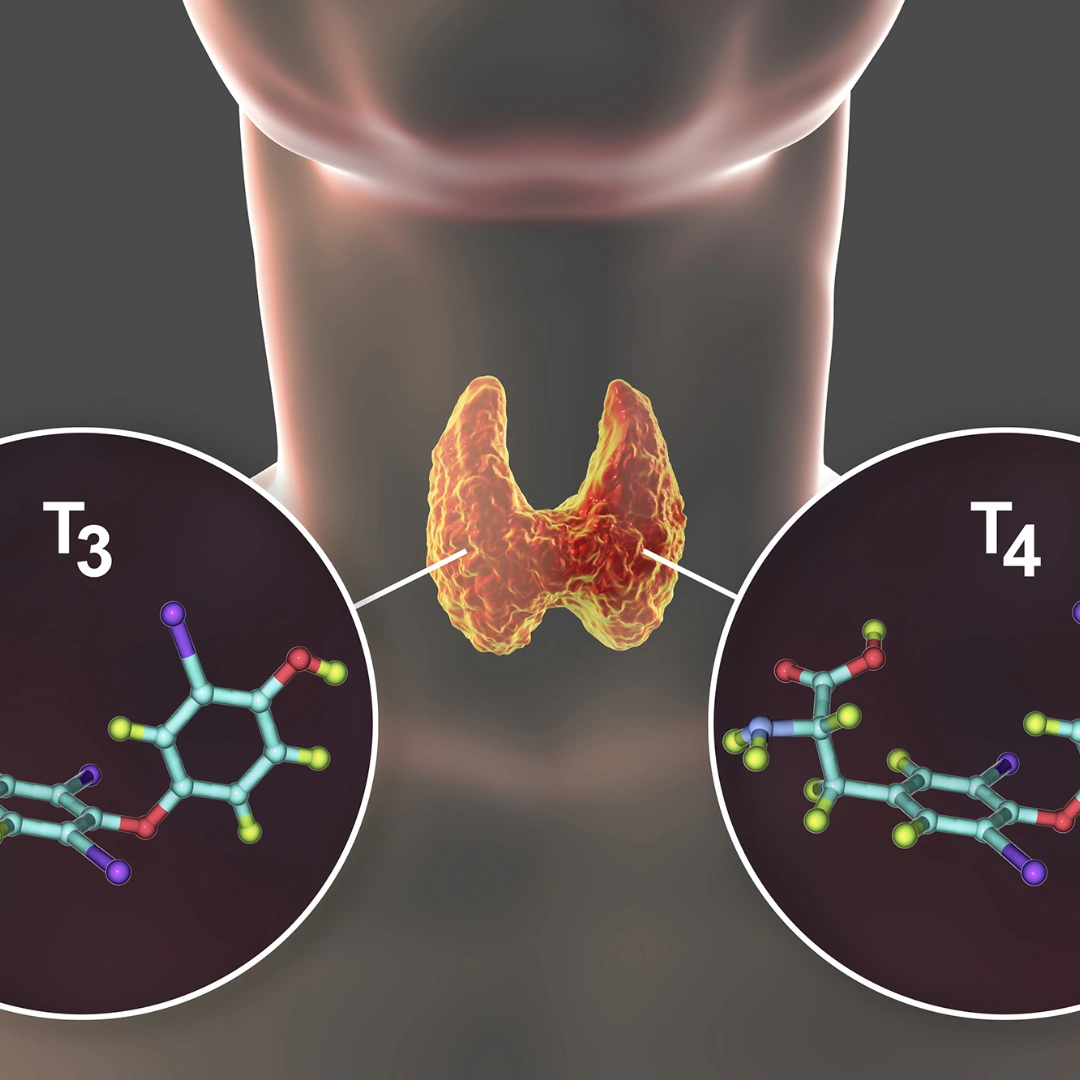

- Thyroid Test

- Thyroid Test